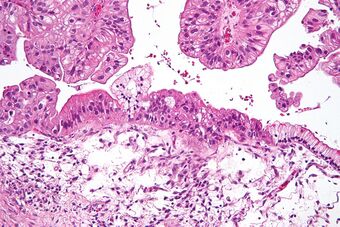

| Micrograph of a mucinous ovarian carcinoma stained by H&E | |

Mucinous adenocarcinomas make up 5–10% of epithelial ovarian cancers. Histologically, they are similar to intestinal or cervical adenocarcinomas and are often actually metastases of appendiceal or colon cancers. Advanced mucinous adenocarcinomas have a poor prognosis, generally worse than serous tumors, and are often resistant to platinum chemotherapy, though they are rare.[29]